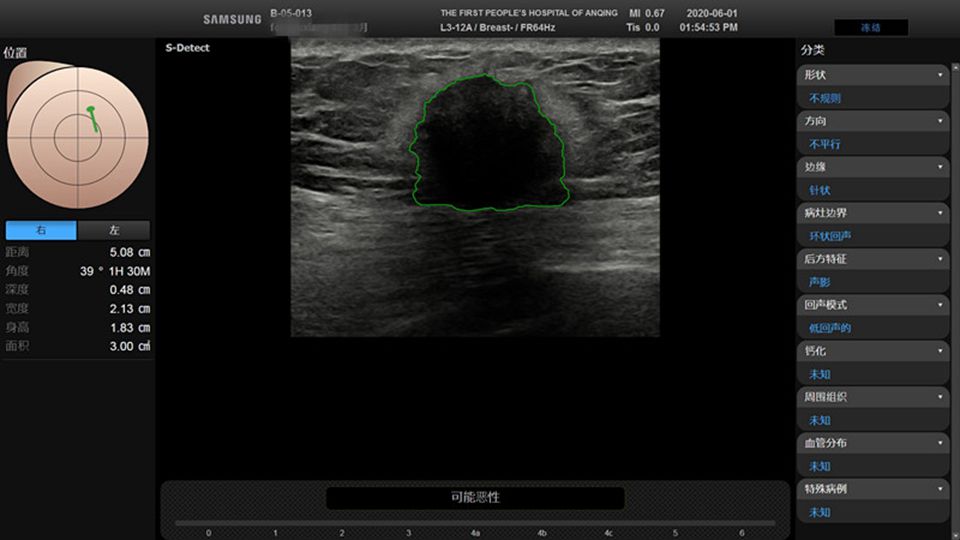

人工智能(S-Detect:提示该结节为恶性)